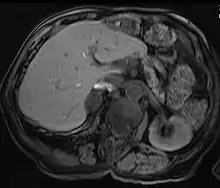

MRI scan T1 with fat saturation - adrenal adenoma

Adrenal adenomas are common, and are often found on the abdomen, usually not as the focus of investigation; they are usually incidental findings. About one in 10,000 is malignant. Thus, a biopsy is rarely called for, especially if the lesion is homogeneous and smaller than 3 centimeters. Follow-up images in three to six months can confirm the stability of the growth.

While some adrenal adenomas do not secrete hormones at all, often some secrete cortisol, causing Cushing's syndrome, aldosterone causing Conn's syndrome, or androgens causing hyperandrogenism.